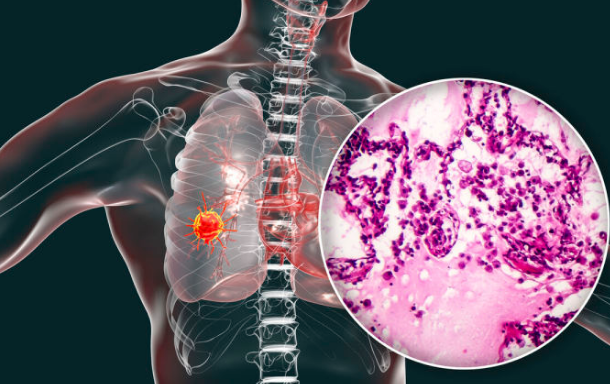

肺癌是一种常见的肺部恶性肿瘤,绝大多数肺癌起源于支气管黏膜上皮,肺癌的分布情况为右肺多于左肺,下叶多于上叶。病发于主支气管、肺叶支气管的肺癌称为中央型肺癌;病发于肺段支气管远侧的肺癌,位于肺的周围部位者称为周围型肺癌。绝大多数肺癌起源于支气管黏膜上皮,但亦有少数肺癌起源于肺泡上皮或支气管腺体。